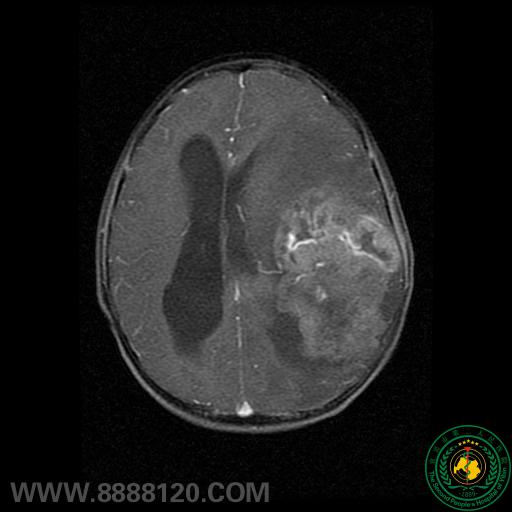

患者头颅MRI示:左侧额颞顶叶巨大不规则混杂信号团块,中线结构明显右移,颅骨明显受侵犯。